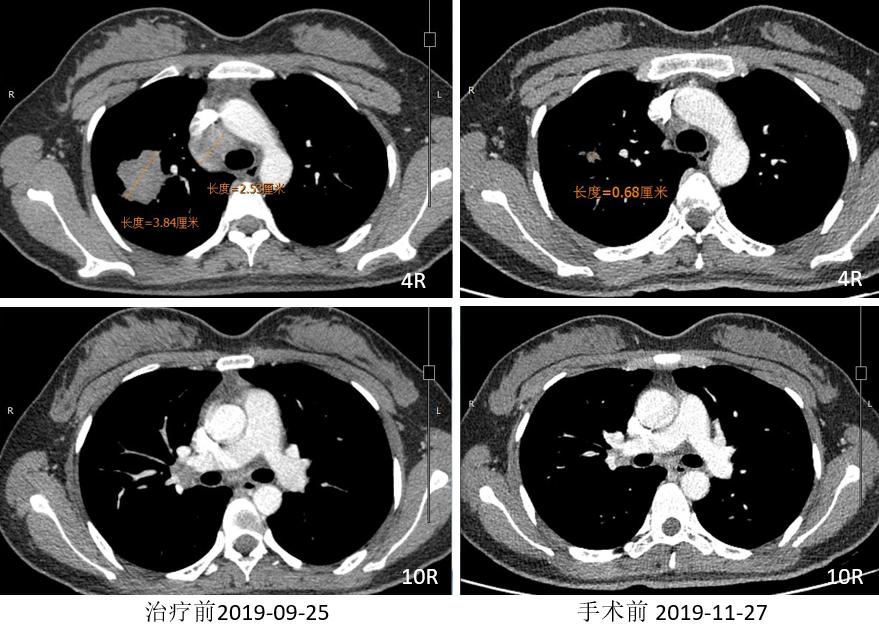

胸部CT

2019.12.10 行“右肺上叶切除术”。

术后病理:(右上叶)浸润性腺癌(腺管型95%,微乳头型5%),(纵隔4R组淋巴结)阴性。病灶内浸润性腺癌(约占20%),见较多区域纤维化伴组织细胞、淋巴细胞浸润,另见胆固醇结晶、多核巨细胞及肉芽肿反应,符合化疗后反应。